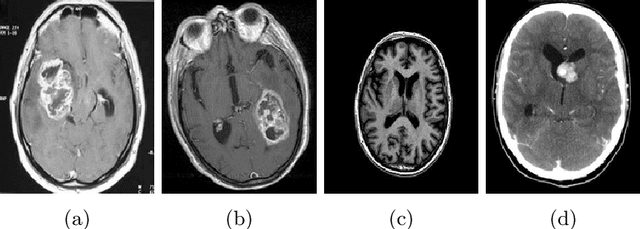

Abstract:This paper presents a research study on the use of Convolutional Neural Network (CNN), ResNet50, InceptionV3, EfficientNetB0 and NASNetMobile models to efficiently detect brain tumors in order to reduce the time required for manual review of the report and create an automated system for classifying brain tumors. An automated pipeline is proposed, which encompasses five models: CNN, ResNet50, InceptionV3, EfficientNetB0 and NASNetMobile. The performance of the proposed architecture is evaluated on a balanced dataset and found to yield an accuracy of 99.33% for fine-tuned InceptionV3 model. Furthermore, Explainable AI approaches are incorporated to visualize the model's latent behavior in order to understand its black box behavior. To further optimize the training process, a cost-sensitive neural network approach has been proposed in order to work with imbalanced datasets which has achieved almost 4% more accuracy than the conventional models used in our experiments. The cost-sensitive InceptionV3 (CS-InceptionV3) and CNN (CS-CNN) show a promising accuracy of 92.31% and a recall value of 1.00 respectively on an imbalanced dataset. The proposed models have shown great potential in improving tumor detection accuracy and must be further developed for application in practical solutions. We have provided the datasets and made our implementations publicly available at - https://github.com/shahariar-shibli/Explainable-Cost-Sensitive-Deep-Neural-Networks-for-Brain-Tumor-Detection-from-Brain-MRI-Images